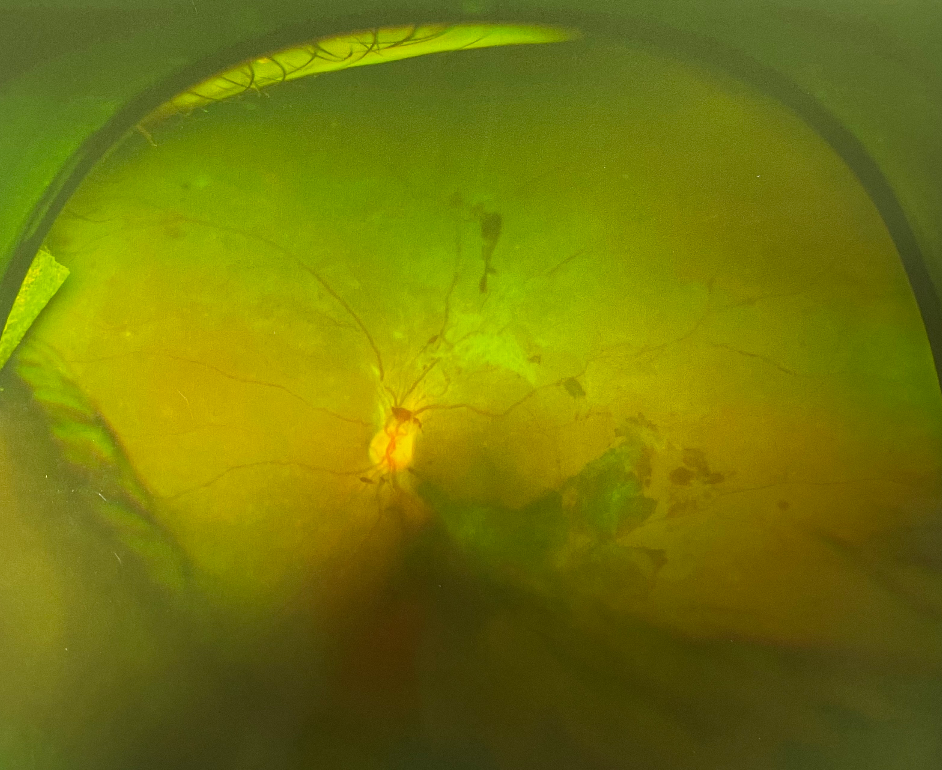

眼底檢查可見靜脈阻塞區(qū)出現(xiàn)大量片狀或火焰狀出血,同時可伴視網(wǎng)膜水腫和滲出。如果視網(wǎng)膜靜脈分支阻塞,眼底出血一般于靜脈阻塞區(qū)局部,視網(wǎng)膜中央靜脈阻塞時,眼底出血廣泛而嚴重。視網(wǎng)膜分支靜脈阻塞累及黃斑區(qū)或視網(wǎng)膜中央靜脈阻塞,患者可出現(xiàn)顯著的視力下降。

患者有糖尿病病史,有些糖尿病患者本人并不知曉,血糖檢查可明確診斷。糖尿病視網(wǎng)膜病變的眼底出血是逐漸發(fā)展的。早期僅表現(xiàn)為少量點狀出血,伴微血管瘤,隨病程進展可出現(xiàn)點片狀出血和滲出。此時患者多無自覺癥狀,一旦病變進展到增生期或出現(xiàn)黃斑水腫,患者可表現(xiàn)為視力下降。如果視網(wǎng)膜新生血管導(dǎo)致視網(wǎng)膜前大量出血或玻璃體出血,患者通常出現(xiàn)視力驟降,嚴重者僅可見手動。

老年性濕性黃斑變性的眼底出血部位一般局限在黃斑區(qū),患者年齡多在50歲以上。臨床表現(xiàn)為突然的視力下降,以中心視力損害為主。OCT檢查可發(fā)現(xiàn)黃斑區(qū)視網(wǎng)膜下新生血管膜(CNV)。濕性黃斑變性晚期也可以出現(xiàn)大面積的視網(wǎng)膜下出血,甚至玻璃體出血,引起更嚴重的視力損害。